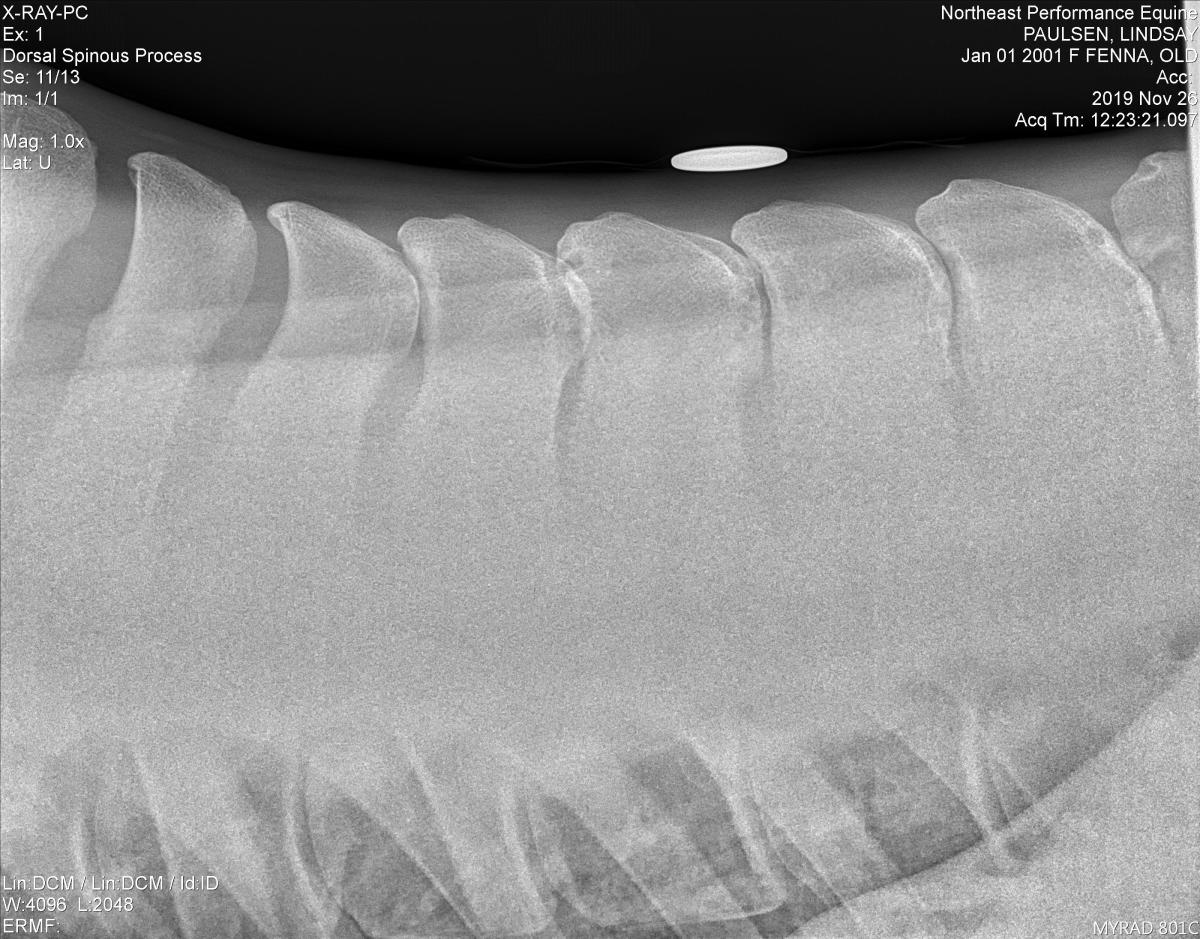

In technical terms, kissing spines are known as interfering or impinging dorsal spinous processes. The dorsal spinous process is the bony part sticking up from each vertebra. Ideally, the spinous processes are evenly spaced, allowing the horse to comfortably flex and extend his back through a range of anatomic positions. But with kissing spines, two or more of these bony extensions get too close, touching or even overlapping in places.

This can lead to restrictions in mobility as well as discomfort, which ultimately can lead to back soreness and performance problems. In fact, kissing spines are one of the leading causes of equine back pain. And over the long-term, they can contribute to additional issues, such as bone cysts or sclerosis, the thickening of bone or new bony deposits at the margins of the dorsal spinous process.

Kissing spines can theoretically happen anywhere in the thoracic or lumbar region of the back—the regions of the spine with a prominent dorsal spinous process, says Dr. Davis. But, he adds, almost all cases will occur in the region from the down-slope of the withers through the thoracic region—from around vertebra T6 through T18. This is the part of the back where your saddle typically rests. Kissing spines is uncommon over the lumbar region, or lower back.

“For a lot of horses, there will be a behavior seen exclusively under saddle, so an under-saddle exam is important, too,” says Dr. Davis. Since it can be difficult to recreate that behavior exactly during the moment of the exam, owners will often share videos of their horse exhibiting the problem behavior. “Once I feel confident the problem is localized to the back, radiographs are the intuitive next step to rule impingement in or out,” says Dr. Davis. Specifically, the vet will do lateral spinal radiographs—X-rays taken from the side that will show the distance between the spinous processes.